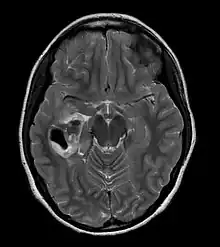

| CT scan of a brain with pleomorphic xanthoastrocytoma. The classic radiographic appearance is one of a superficially situated tumor, here a mural nodule, associated with an underlying cyst. |